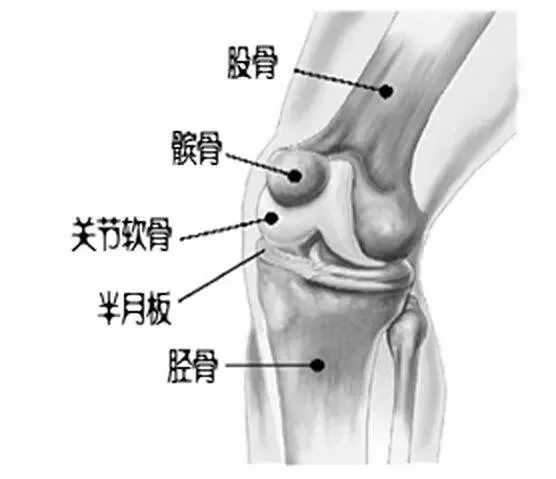

了解疾病前,先来了解膝关节的正常结构。

股骨、胫骨和髌骨共同构成膝关节的骨性结构,在互相接触的关节面,都覆盖一层光滑的关节软骨,同时股骨和胫骨之间有半月板,关节腔内有关节液。

三者相互配合润滑关节、减少摩擦,在运动中缓冲压力,共同维护关节的正常功能和状态。